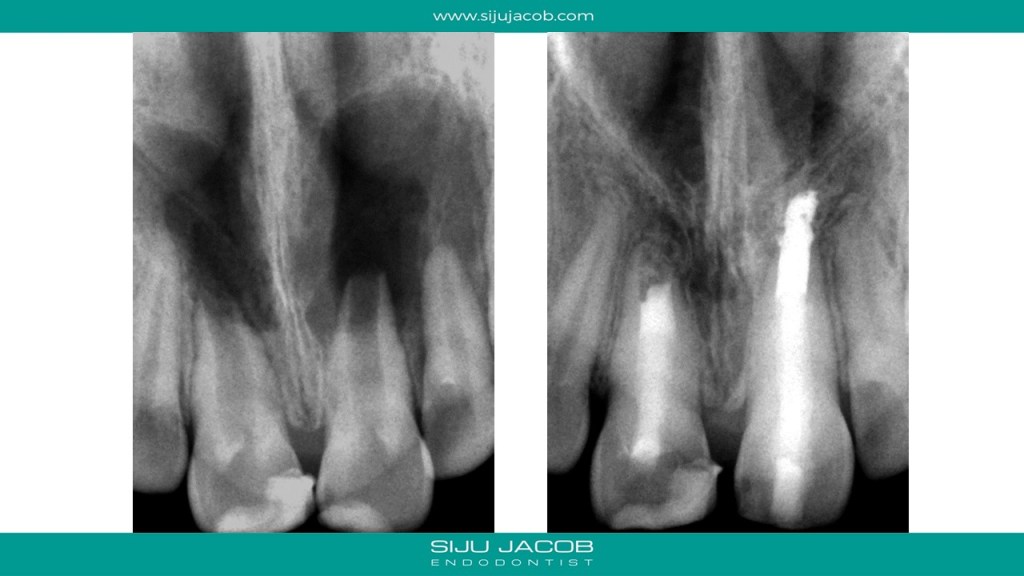

This was probably the largest lesion I ever treated. It had several interesting characteristics. It would be tough to explain with just pics. So, I made it into a short presentation